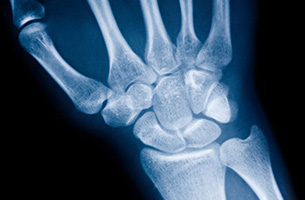

손목터널증후군의 진단

초음파

손목터널 내 구조, 부종·낭종·종양 확인

MRI

드물게 다른 압박 원인 감별 필요 시 시행